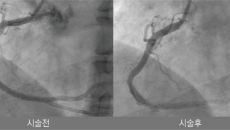

나은병원, 인천·경기 첫 '혈관 내 쇄석술' 성공…석회화 관상동맥 치료 새 이정표

[스포츠조선 장종호 기자] 나은병원이 중증 석회화 관상동맥 질환 치료에 있어 새로운 이정표를 세웠다. 나은병원 심장내과 심혈관- 2026-01-22 11:59